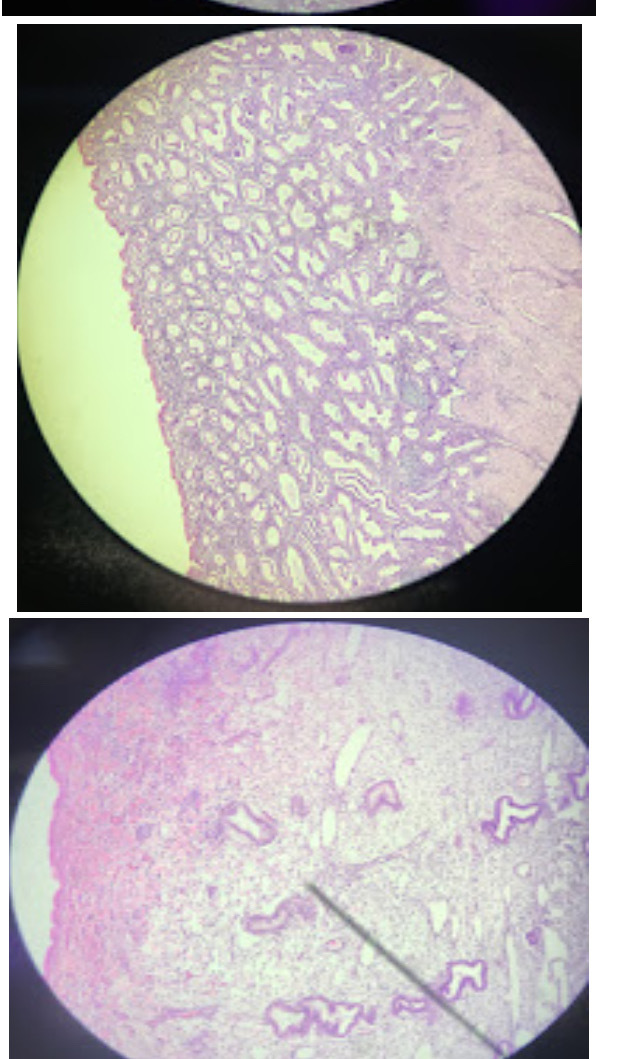

Uterus Menstrual

Phase 1

epithelium and cellular structure is gone

Uterus Secretory

Phase 3

jagged

Uterus Proliferative

phase 2

entatct epithelium- round to oval shaped